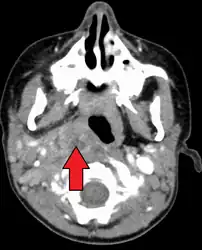

Large retropharyngeal abscess as seen on CT -

Large retropharyngeal abscess as seen on CT